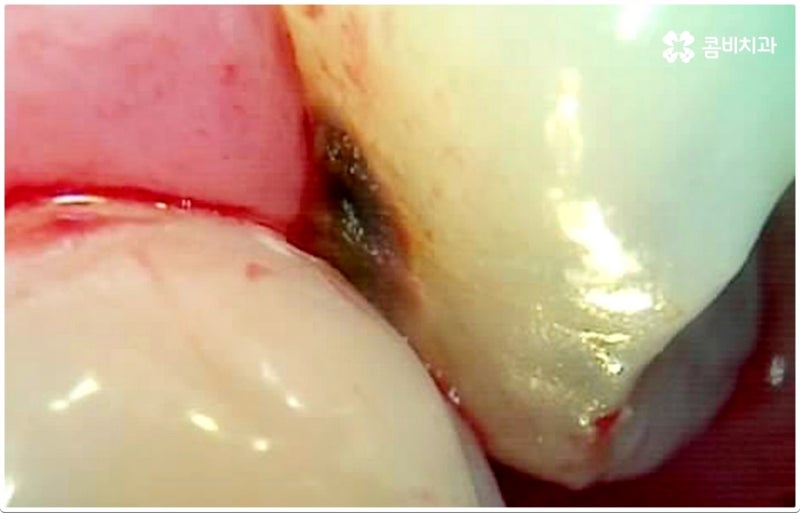

#症牙# 인접치아우식증 그러나 인접치아가 서로 맞닿아 우식에 영향을 미치게 되면 자신도 모르게 진행되어 증상을 유발할 수 있습니다. 또한 육안으로 확인이 쉽지 않기 때문에 무시하는 분들도 적지 않습니다. 따라서 상태가 악화되어 통증을 유발한다면 치료 과정이 더욱 복잡해질 수 있습니다. 그렇기 때문에 치아 사이의 충치는 세심한 관찰이 필요합니다. 특히 치석은 양치질을 잘 해도 치관 주변에 쌓이게 됩니다.

양분을 씹어먹고 치석이 쌓이면서 치아 사이에 충치가 생기는 것을 볼 수 있습니다. 이 시점에서 증상 부위가 하나가 아니라 두 개의 영구 치아에 영향을 미치고 있음을 알 수 있습니다. 이 과정에서 신경 조직과의 근접성으로 인해 다양한 문제가 악화될 수 있습니다. 그렇기 때문에 적절한 시기에 치료가 이루어져야 합니다. 그렇지 않으면 근위부 우식증이 내부 조직으로 확장되어 자연 치아 기능이 상실될 수 있습니다.

관리하기 어려운 위치에 있기 때문에 찾기가 어렵습니다. 특히 치아의 외측은 법랑질로 이루어져 있습니다. 여기 구조도를 보면 헤드가 두꺼워진 것을 알 수 있습니다. 하지만 그에 반해 옆구리는 가늘고 신경에 가까워 취약하다는 것을 보여준다. 특히 어금니 뿐만 아니라 앞니에 해당하는 앞니와 송곳니에도 발생할 수 있습니다. 따라서 앞니 사이의 충치는 두 개 이상의 치아와 인접해 있는 경우가 많기 때문에 치료를 위해서는 두 개의 치아도 필요하다. 그러나 점진적으로 발달하므로 초기 단계에서 발견하기 어려울 수 있습니다. 앞으로 치아우식증이 생기면 그 문제를 모르는 분들이 적지 않습니다. 근위부 우식 수술의 어려움은 상상할 수 있습니다 손상된 치질을 제거하는 것이 어렵고 치료가 어려운 것은 의심의 여지가 없습니다. 그래서 교합면에서 윗부분으로 삭제된 글자 모양의 와동을 볼 수 있습니다. 특히 벽의 한쪽이 제거된 것을 볼 수 있습니다. 여기서 단순히 레진으로 채우면 씹는 힘을 견디지 못하고 떨어질 수 있습니다. 그래서 우리는 모델을 금이나 단단한 레진으로 만듭니다. 이렇게 제작된 보철물은 서로 접착되어 원래의 기능을 회복하는 것을 볼 수 있습니다. 그러나 앞니 사이의 충치가 넓지 않은 경우에는 부분적 제거 후 레진으로 채우는 것으로 볼 수 있습니다. 감기 증상과 통증이 황금 시간대에 발생하면 근관을 점차적으로 청소해야 할 수 있습니다. 즉, 신경을 제거하고 자연치아를 보존하기 위해서는 크라운을 만들어 치아 전체를 덮어야 합니다. 언제 Zoom을 받았습니까? 건강 보험 신청 및 비용을 살펴보겠습니다. 치근 근처의 치석이나 치태를 제거하는 시술일 수 있습니다. 이것은 잇몸의 질병이나 염증을 예방하는 데 도움이 됩니다. 즉, 19세 이상이면 누구나 1년에 한 번 줌을 돌보고 보험에 가입할 수 있다. 그리고 매년 1월 1일에 갱신됩니다. 그러나 비용이 건강 보험으로 보장되는 경우에도 차이가 있을 수 있습니다. 특히 병원이나 의원의 종류에 따라 비용이 달라지거나 주말 및 야간진료에 따른 추가비용이 발생할 수 있습니다. 또한 치료 전에 엑스레이를 특별히 촬영했는지 여부에 따라 추가 요금이 부과됩니다. 하지만 치과에 장기간 내원하시거나 흡연이 재발하는 경우에는 정밀진단을 받으시는 것을 권해 드립니다. 건강한 영구치는 습관으로 지켜야 합니다. 일반적으로 양치질을 할 때 이를 닦는 사람들이 적지 않다. 그래서 닿는 면이 잘 닦이지 않습니다. 따라서 치실을 사용하면 달라붙는 세균 덩어리와 이물질을 제거하기 위해 만지는 표면을 쓸어내는 것입니다. 따라서 건강하고 깨끗한 구강을 유지하기 위해서는 보조적인 제품을 적극 권장한다. 또한 질병의 증상이 없더라도 초기에 발견할 수 있기 때문에 3~6개월마다 치료를 받는 것이 가장 좋다. 치석과 플라그는 씹는 영양분으로 인해 치아 사이에 충치를 유발합니다. 점차 병이 악화되고 치주질환까지 발생하게 되어 조직손상을 일으킬 뿐만 아니라 점차적으로 치아가 흔들리게 되므로 정기적으로 세안하고 체크하는 것이 유익합니다. 특히 수술 후에는 스스로 관리가 필요하다는 사실을 잊지 마세요. 즉, 서로 맞닿아 있는 마주보는 인접면에 우식이 발생할 수 있다. 따라서 치실과 치간칫솔을 계속 사용해야 합니다. 라온치과병원 대구광역시 수성구 동대구로 312 범머림타워 8층, 9층, 11층 이전 이미지다음 이미지이전 이미지다음 이미지